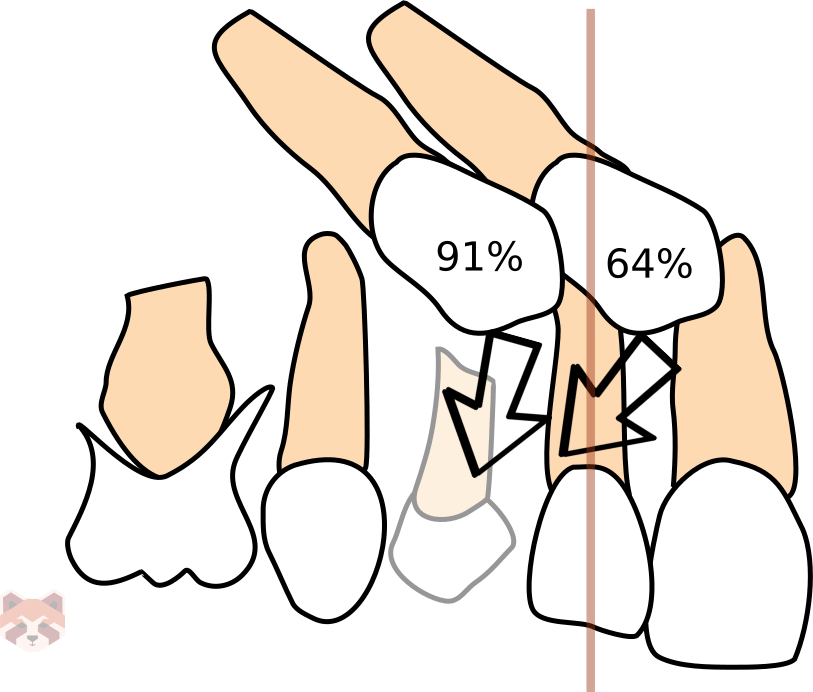

If an impacted canine is diagnosed early, the removal of the deciduous canine could be indicated. The removal of the deciduous canine before the age of 11 will normalize the position of the ectopically erupting permanent canines in 91% of the cases if the canine crown is distal to the midline of the lateral incisor. The expected success rate is only 64% if the canine crown is mesial to the midline of the lateral incisor. Other treatment options include: